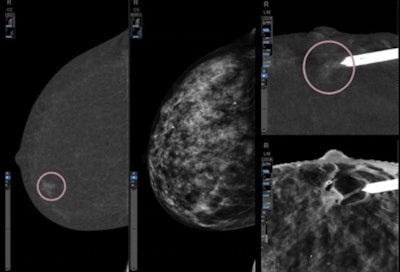

Serena Bright is a new contrast-enhanced guided biopsy technology that allows these exams to be performed on the same mammography equipment, rather than requiring patients to be transferred to a breast MRI scanner.

Serena Bright is based on the company's SenoBright HD contrast-enhanced spectral mammography (CESM) technology, which highlights unusual blood flow patterns and can be performed after an inconclusive mammogram or ultrasound exam. SenoBright HD is offered as an option on Pristina.

GE is also discussing the ProFound algorithm from iCAD for detecting malignant soft-tissue densities and calcifications, providing a numerical confidence score on whether a case is malignant.